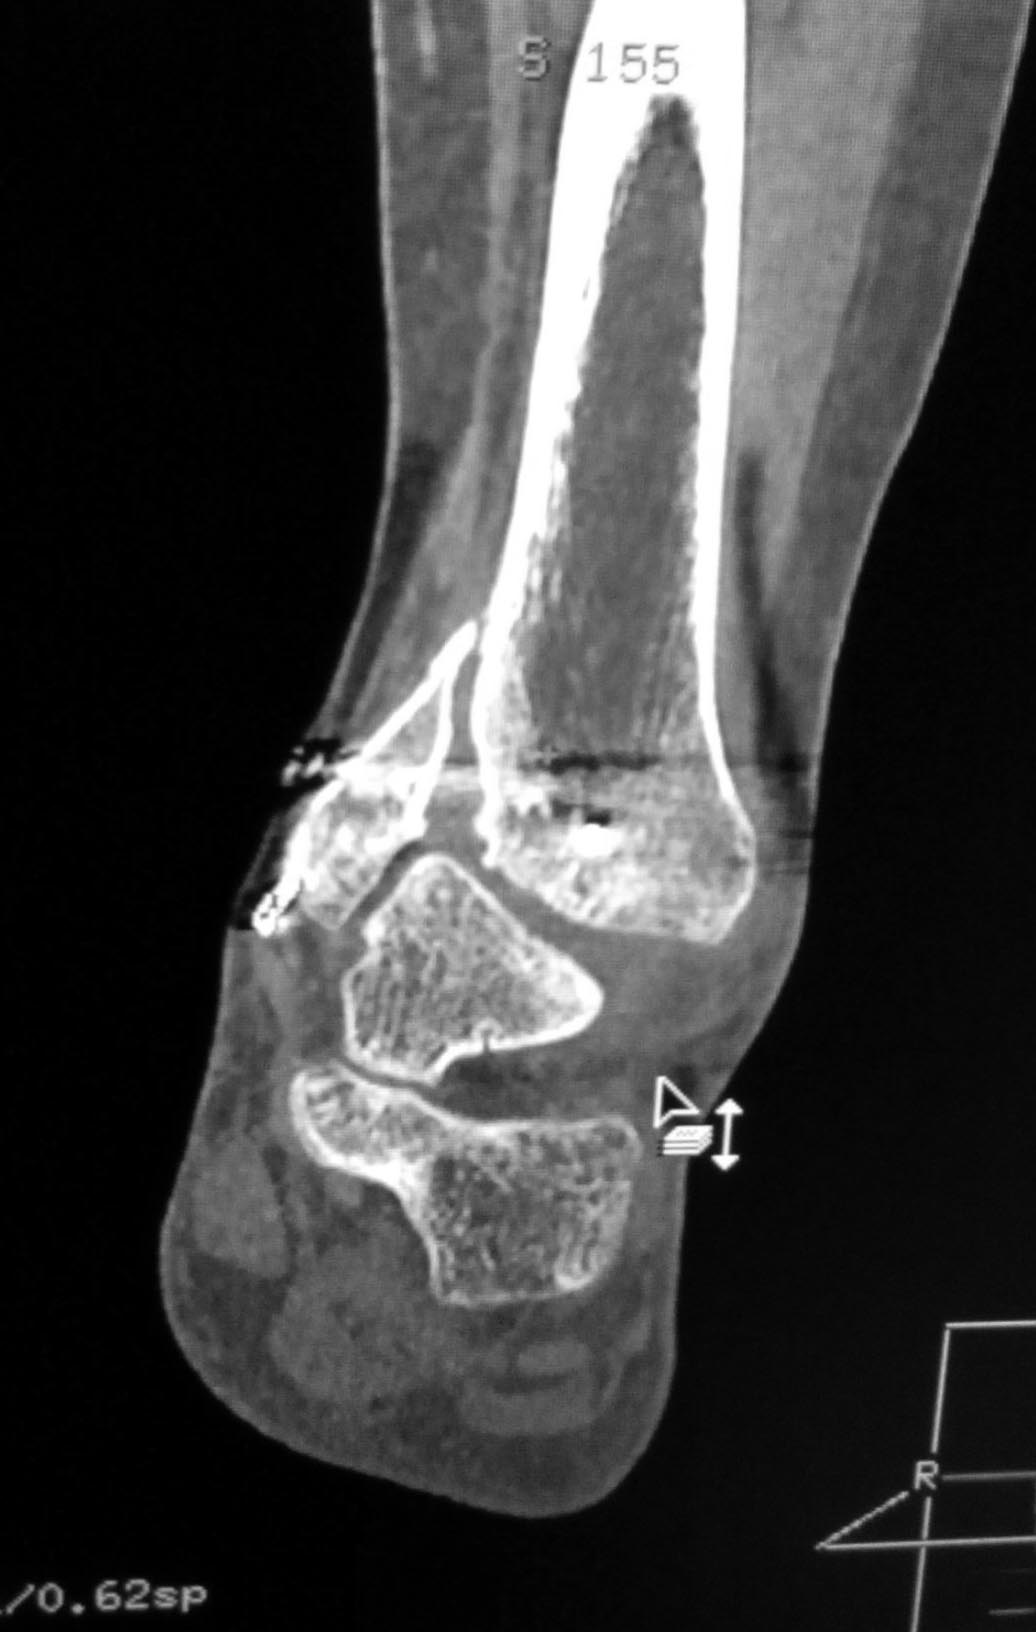

Мужчина, 1987 г.р. получил травму 10.2014. ДТП. Закрытый двухлодыжечный перелом костей костей левой голени, перелом заднего края большеберцовой кости с подвывихом стопы кзади, кнаружи.

Наложен дистрактор. Операция 10.2014: закрытая репозиция, остеосинтез спицами, винтами. В дальнейшем произошло ожидаемое усугубление нарушений взаимоотношений в голеностопном суставе.

Какой план лечения,на Ваш взгляд, предпочтительнее в данном случае? Возможно ли одномоментно устранить подвывих или только на аппарате Иллизарова? Первичные снимки после травмы отсутствуют. Критично ли "растоптана" латеральная суставная поверхность большеберцовой кости?

Мне кажется, что вопрос, поставленный Вами: "Возможно ли одномоментно устранить подвывих или только на аппарате Иллизарова?", отражает не совсем ясное понимание ситуации. Что значит устранить подвывих? А пластику ложных суставов внутренней лодыжки и заднего края большеберцовой кости не нужно делать? И ось голеностопного сустава нужно исправлять. То есть делать остеотомию наружной лодыжки (если она срослась, по снимку не очень понял). Артродез голеностопного сустава в такой ситуации очень сложен. Если же добиться сращения всех переломов в правильном положении, артродез вполне можно отсрочить на несколько лет, что для молодого пациента достаточно важно. Но в конечном счете все определяется Вашим умением и ясным представлением того, чего Вы хотите добиться своей операцией. Во вложении - в чем-то похожий случай. Оперировал эту пациентку 23 лет 11 лет назад через 8 месяцев после похожего на представленный Вами остеосинтез. На первой операции перелом малоберцовой кости в нижней трети был просто не замечен. За счет восстановления оси быстро развившийся артроз протекал благоприятно. В результате артродез был выполнен только в прошлом году, через 10 лет после второй операции. И боли беспокоили пациентку только в течение года перед артродезом.